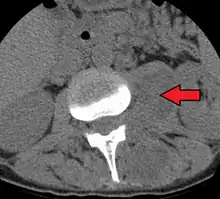

Paraspinal abscess in the psoas muscle | |

Psoas abscess is a collection of pus in the iliopsoas muscle compartment.[1][2] It can be classified into primary psoas abscess (caused by hematogenous or lymphatic spread of a pathogen) and secondary psoas abscess (resulting from contiguous spread from an adjacent infectious focus).[2]

Psoas abscess may be caused by lumbar tuberculosis. Owing to the proximal attachments of the iliopsoas, such an abscess may drain inferiorly into the upper medial thigh and present as a swelling in the region. The sheath of the muscle arises from the lumbar vertebrae and the intervertebral discs between the vertebrae. The disc is more susceptible to infection, from tuberculosis and Salmonella discitis. The infection can spread into the psoas muscle sheath.[3]